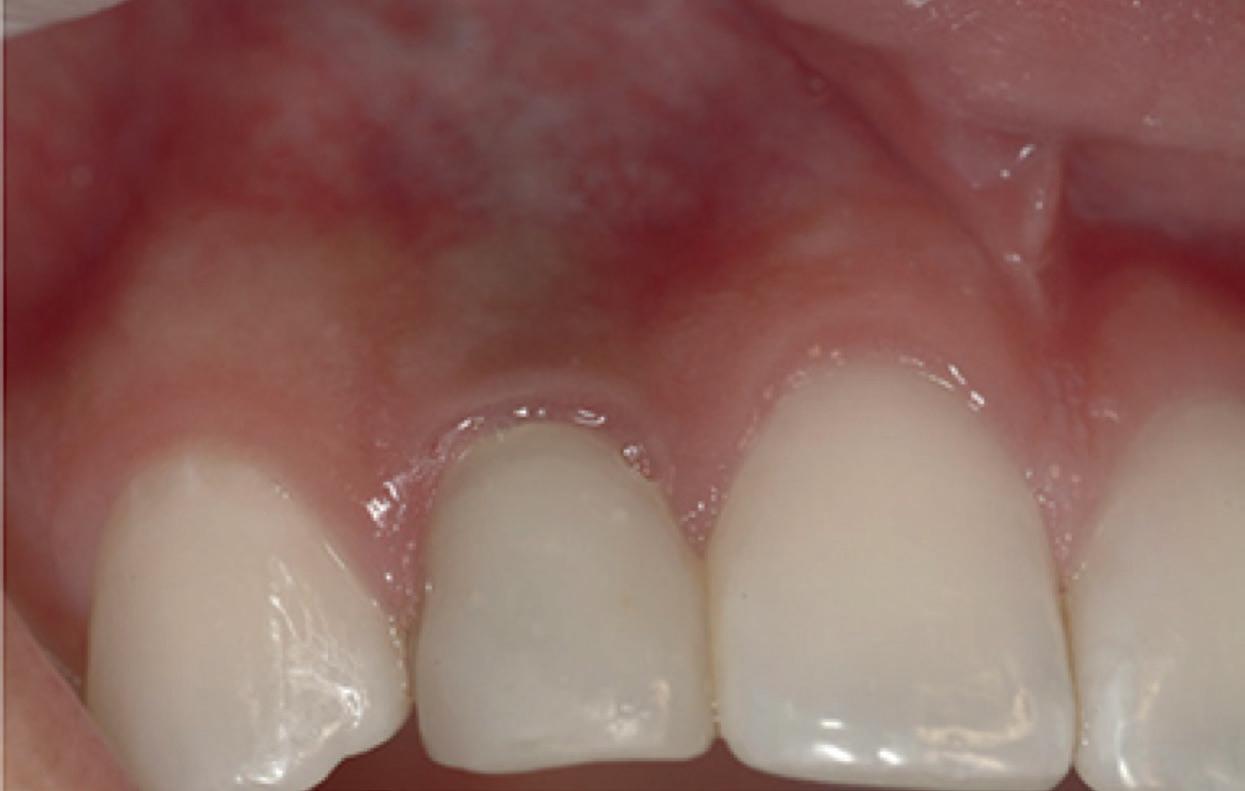

Mevrouw werd naar het Dental Design Center verwezen om een complex probleem aan het bovenfront te beoordelen en indien mogelijk te behandelen. Tien jaar geleden zijn er om esthetische redenen op de 12, 11, 21 en 22 kronen geplaatst. Helaas bleek achteraf een wortelkanaalbehandeling van de 22 noodzakelijk. Na een aantal jaar ontstond er weer een infectie apicaal aan de 22 en werd er een apex uitgevoerd. Helaas had deze behandeling niet het beoogde resultaat. Twee weken voordat ze bij mij op consult kwam, is het element geëxtraheerd en is er een partiële plaat geplaatst als tijdelijke oplossing (foto 1-3).

Na de IPP (esthetisch/functionele) analyse blijkt dat de gezichts- en faciale mediaan niet geheel overeenkomen en dat de gingiva lijnen van het bovenfront niet helemaal parallel lopen met de interpupillaire lijn. Na overleg met mevrouw kiest zij ervoor om dit niet orthodontisch te laten corrigeren. Mevrouw

1 2 3 23

heeft de nadrukkelijke wens om geen brugconstructie te krijgen. Om die reden is een etsbrug of een conventionele brug geen optie. Daarom bestaat het behandelvoorstel uit vier losse kronen waarvan de 22 implantaat gedragen zal zijn. Een gedetailleerd onderzoek van de regio 22 is noodzakelijk (foto 4-6).

De flap en graft worden met poly-propelene 6.0 hechtingen gefixeerd. De tijdelijke reconstructie wordt herplaatst (foto 17-20).

Na 4-6 weken kan het aangebrachte healing abutment worden vervangen door een tijdelijk abutment. Deze wordt aan de kunststof reconstructie verbonden om zo de gingiva ter plaatse van de 22 te vormen. Zo lijkt het of er geen implantaat maar nog steeds een wortel aanwezig is, wat het esthetisch eindresultaat ten goede zal komen (foto 21-23). Vanaf 4-6 maanden ziet het weefsel er gezond uit. Nu kan met de uiteindelijke restauratiefase worden gestart (foto 24 en 25).

De dentale mediaanlijn is rechtop gezet, maar staat niet helemaal gelijk met de faciale mediaan. Echter, mevrouw is functioneel en esthetisch naar tevredenheid afbehandeld (foto 27-30).